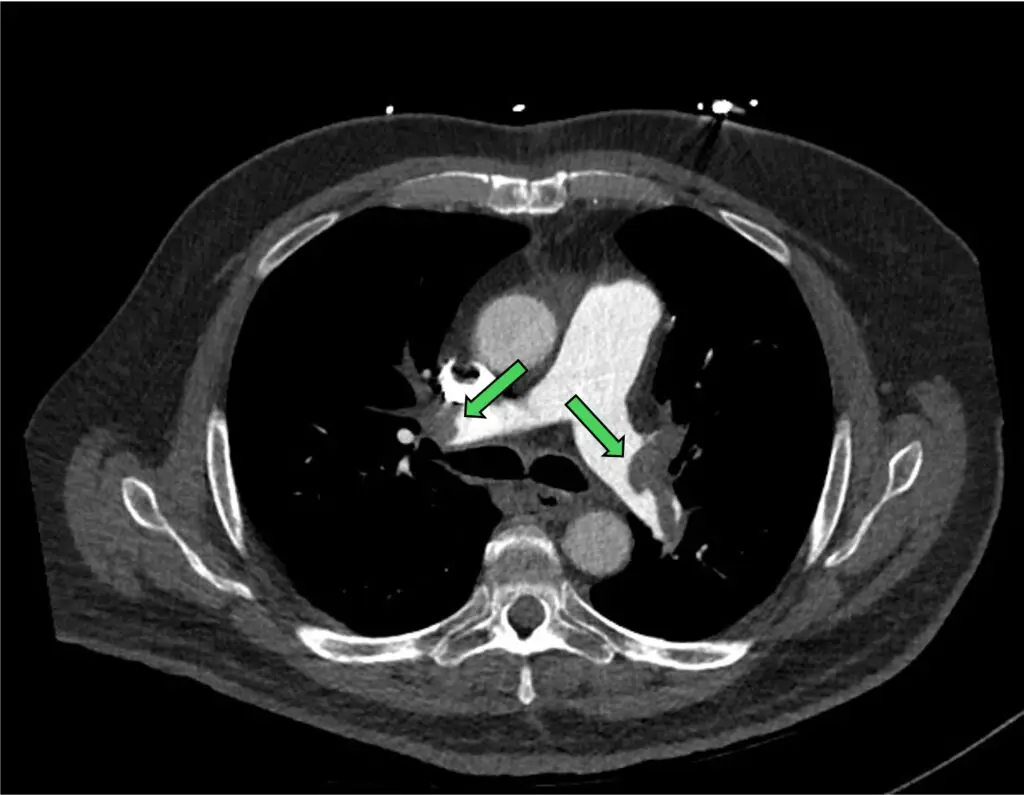

Figure 4: near occlusive clot in both the right and left main PA

Figure 5: non-occlusive clot in one of the segments of right PA